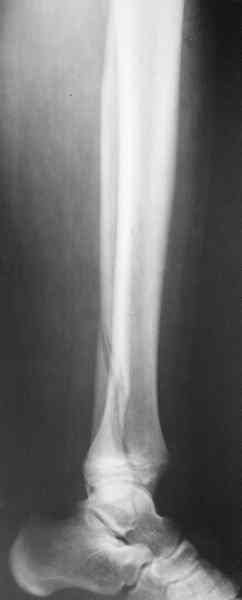

Уважаемый коллега! Обычно, хирургичское лечение переломов пилона начинают с остеосинтеза малоберцовой кости (чего не продемонстрировали коллеги из Новокузнецка). В Вашем случае нет убедительных данных за перелом малоберцовой кости, так что, видимо, этот этап вы пропускаете. После чего переходят собственно к пилону - основные усилия в лечении которого необходимо направить на устранение импрессии (отчетливо видна на боковой R-грамме), затем пластика дефекта ну и накостный остеоинтез платиной, коих достаточно много. Хотел бы предостеречь Вас от: закрытой "малоинвазивной" техники в данном случае, так как для устранения импрессии малоинвазивно необходим определенный опыт и начинать с этого я бы не стал, использовать пластину Pilon Plate-имплант сложный в установке и , опять же, требует определенных навыков. Я бы синтезировал традиционной пластиной "лист клевера" с угловой стабильностью.

Есть смысл начать с наложения дистрактора голень-стопа. Лигаментотаксис может очень существенно помочь с репозицией. При переломе малоберцовой кости этот подход позволяет не тратить время на ее остеосинтез. Больших участков импрессии суставной поверхности не видно, перелом больше по типу раскалывания. Это делает возможной полностью закрытую репозицию с фиксацией либо аппаратом, либо компрессирующими винтами и аппаратом, либо пластиной малоинвазивно.

1 - перелом закрытый;

2 - соотношение осей голени и стопы практически идеальное;

И какой смысл переводить закрытый в открытый, подвергать операционным рискам пациента с ГБ в 60 лет? Тем более, что после операции наступать на ногу ему никто не разрешит минимум 3 месяца. Моё мнение - только консервативно и под регулярным контролем и дозированным ЛФК, причем движения в суставе начинать не познее конца 6-ой недели, а лучше с 5-ой.